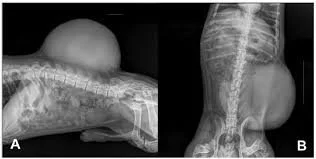

xray of skin mass bushnell animal clinic

In some cases, imaging such as X-rays or ultrasound may be used to evaluate whether a tumor has spread to other parts of the body.